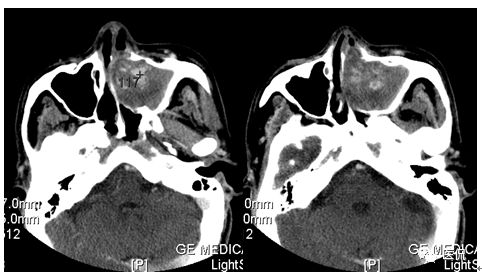

增强水平位FST1WI

CT平扫及增强示:左侧上颌窦及鼻腔可见软组织密度影,呈膨胀性生长,周围骨质压迫性吸收破坏,累及左眶,病灶密度不均匀,周边区可见点状钙化,增动脉期轻度强化,局部见小灶性稍高密度区,静脉期病灶内见不均匀明显强化,CT值最高达117HU,延迟期强化范围有所增大。

影像学表现呈软组织密度,多不均匀,表现为高低混杂密度,病变窦腔内息肉、血肿、坏死、感染共存,是病灶密度不均匀的主要原因,息肉反复出血、血管机化亦为其成因之一。病灶内钙化,可为团块状或小片状,可能为病变组织坏死后钙质沉着所致。由于病变组织内有大量炎性细胞浸润和丰富的毛细血管,增强后常有强化。有文献报道病灶增强中心区强化不明显,外周呈轻度强化,推测病灶内虽然血管丰富,但中心区容易出现血流动力学障碍,血管内常有血栓形成,中心区易发生出血坏死,另外,可能与增强扫描延迟时间选择不当有关。

本例病灶较大,周围骨质可见吸收破坏,并累及眼眶,病灶内少量钙化,增强扫描具有一定特征性,表现为动脉期轻度强化,局部见小灶性稍高密度区,静脉期病灶局部呈明显强化,CT值最高达117HU,延迟期强化范围有所增大,呈延迟渐进性强化的特点,推测为病灶内出血所致。